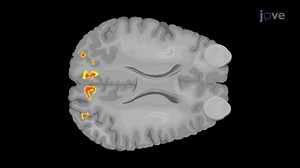

Video: Blood Oxygen Level-Dependent Functional Magnetic Resonance Imaging of the Visual Cortex - Experiment

jove.com